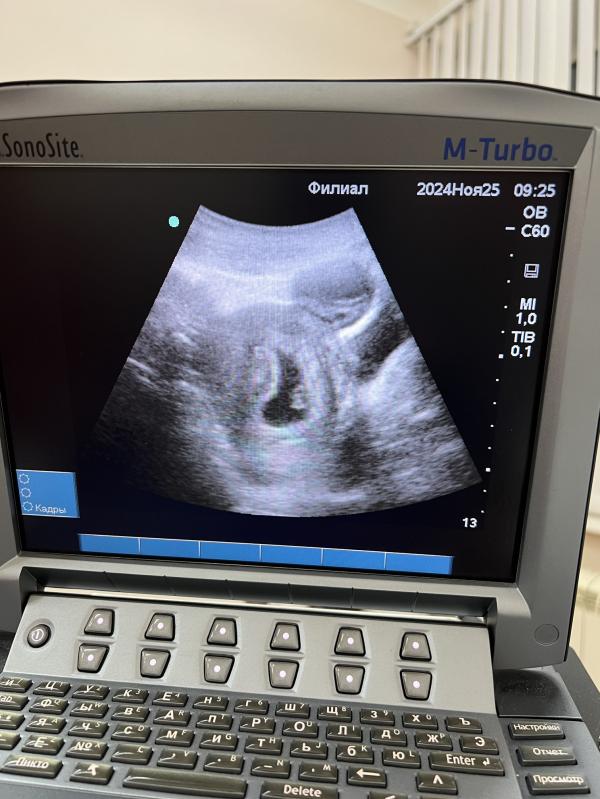

Очередное узи! (Четвертое уже🙈)

ЧСС 138, ктр 1,15 см,

Кисту еще увидела, вроде киста желтого тела.

И тонус по задней стенке. Половой и физический покой, и сажусь на дюфастон 🙈